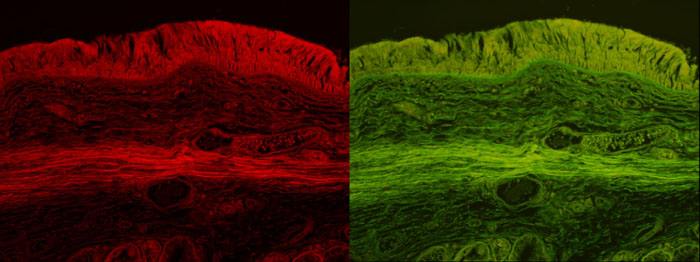

2)気管の壁 粘膜と平滑筋

Optiphoto 対物x10 撮像x2.5 LED電流 0.6A

カメラ Lumix DMC-G5 左G励起 iso 200 露出時間 5sec, 右B励起

iso 200 露出時間 5sec